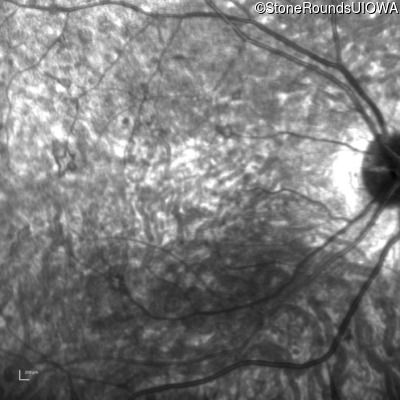

Infrared Fundus Photograph - Right - 5/200 sc

Exemplar